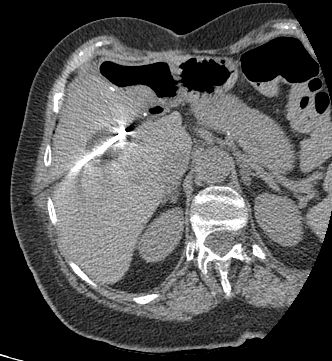

69 year old female with a known history of colon cancer who presents with a new liver mass on surveillance imaging.